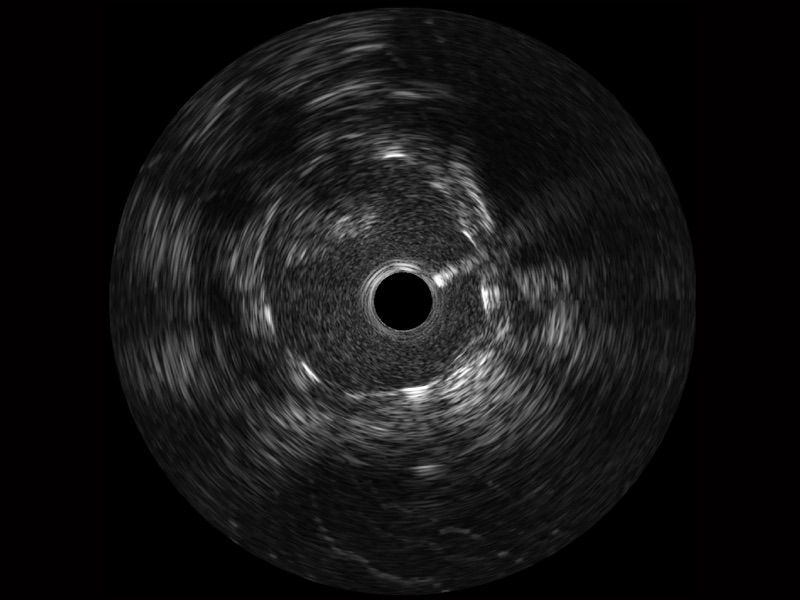

1xBET宽频IVUS图像

对比传统IVUS导管成像,1xBET宽频IVUS图像的近场支架梁显影更细腻,远场中膜外血管仍清晰可辨,兼顾远中近,兼顾分辨力与穿透深度